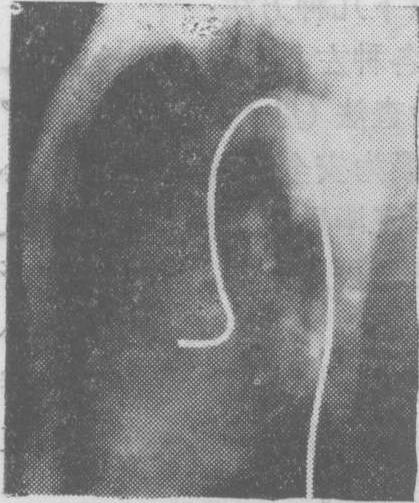

(2) 选择性左心室和主动脉造影: 选择性左心室造影可通过经胸壁穿刺左心室法、穿刺心房间隔左心导管检查法或经动脉逆行左心导管检查法(见“左心导管检查” 条) 等来施行。其中以后者最为安全可靠,并可同时施行选择性主动脉造影,尤以经皮肤穿刺股动脉法送入猪尾状左心室造影心导管最为简便(图3)。

术前准备除需作碘造影剂的过敏试验外,与经动脉逆行左心导管检查同。如从上肢动脉或颈外动脉送入心导管则以选用右侧较易送到升主动脉,如从下肢动脉送入心导管则选用左、右两侧股动脉均可。心导管顶端进入升主动脉后有时通过主动脉瓣有困难,此时顶端一段弯成圆圈状的心导管例如猪尾状心导管则较易送入。猪尾状心导管一般通过经皮股动脉穿刺法送入,当其套在导引钢丝外时,其顶端弯成圆圈部分即变直,便于经动脉穿刺口进入,撤出导引钢丝则顶端恢复圆圈状。当顶端经过主动脉瓣进入左心室有困难时,还可将导引钢丝再置入其管腔,但不到达顶端圆圈状部分,这样心导管的硬度加强而顶端仍呈圆圈状,更易于送入左心室。注射造影剂时心导管顶端的位置宜游离在心室腔中,并离二尖瓣较远,以避免造影剂注入心肌发生危险或反流入左心房,人为地造成二尖瓣关闭不全的假象。摄片取右或左前斜位投照。